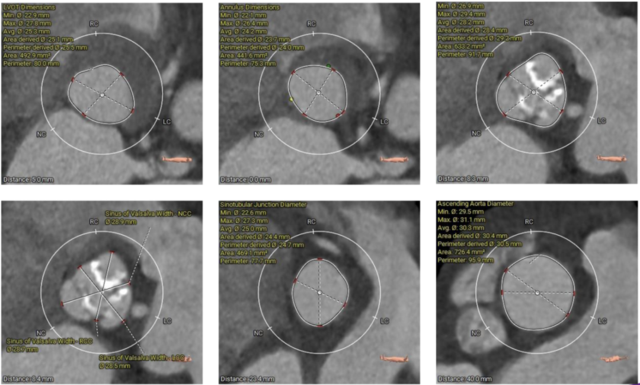

▲患者术前CT评估

▲主动脉根部测量

该病例主动脉根部结构较小,并且左冠脉开口高度距离瓣环较近,只有10.2mm,有一定的冠脉阻挡风险,手术团队讨论后决定在TAVR时进行冠脉保护,提前将冠脉通路准备好,并且结合球囊扩张及瓣膜释放工作位综合评估。

综合以上分析及病例特点,手术策略如下:三叶式主动脉瓣,轻度钙化伴瓣叶增厚,左冠开口较低,右冠高度可,综合瓦氏窦内径、窦管交界内径等因素考虑,左冠行冠脉保护,非横位心,弓距弓角可,左室内径可,双侧入路血管走形良好,整体入路血管条件可。计划使用20mm球囊预扩,预装23型号瓣膜,释放高度零位开始释放,最终依据术中情况决定是否做烟囱支架冠脉保护技术。